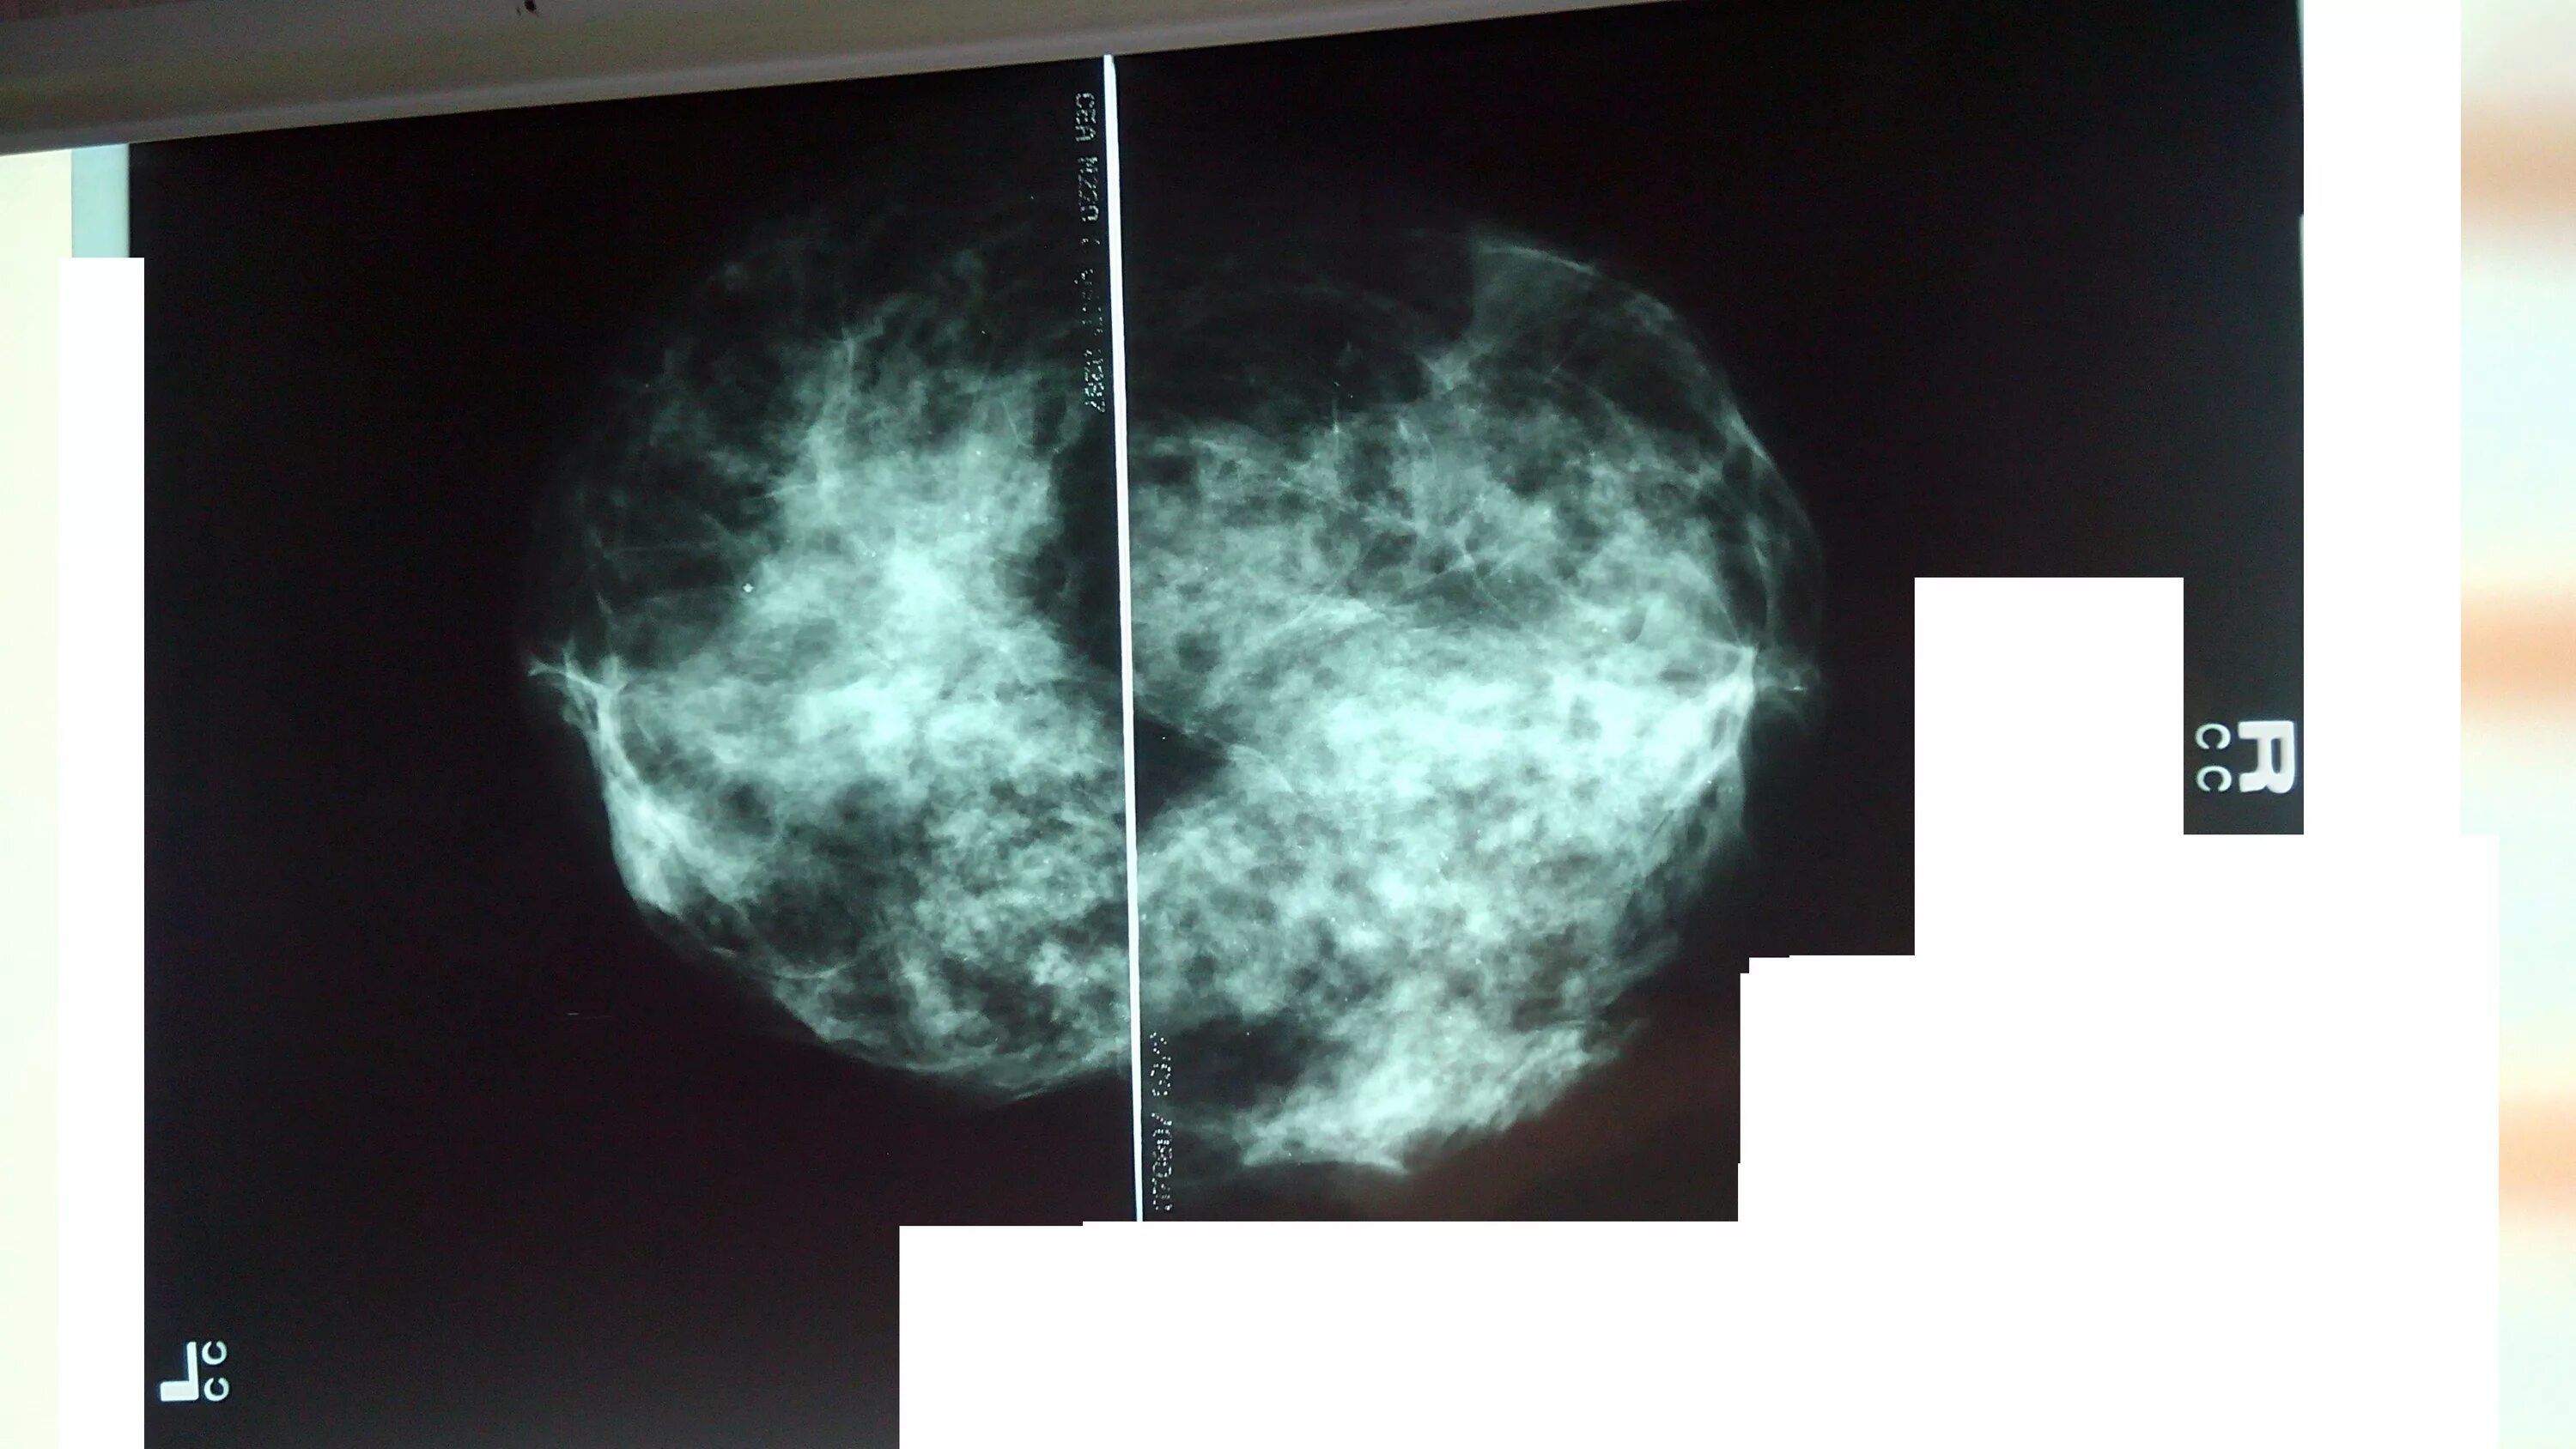

Сгруппированные микрокальцинаты